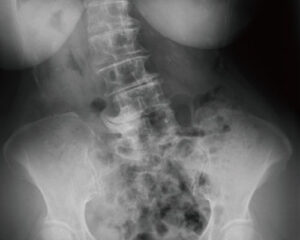

椎間板の変性段階(D1~D6)

D5 10~15年経過

椎間板の変性が慢性化したステージで、サブラクセーションが10~15年放置されている状態になります。椎間板の水分は放出され、椎間板スペースの元の厚みの1/3まで減少し、骨の変形が進みます。上下の椎骨がより接近し可動性がより制限され、神経への負荷を避けるための防御反応により、カルシウムが沈着しより補強を始めます。ケアをしても椎間板スペースや骨の変形には変化が見られませんが、神経機能が改善することは可能です。